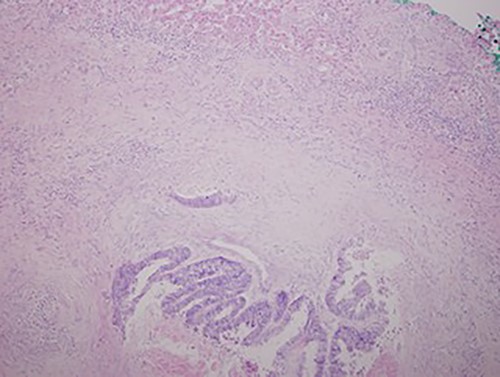

Low magnification power view of liver tissue with metastatic deposit from colon adenocarcinoma. (hematoxylin–eosin original magnification ×100).

A chest X-ray at the time of admission showed right upper lobe mass (Fig. 1). Tru-Cut biopsy was performed and confirmed the diagnosis of non-small cell carcinoma (Figs 2 and 3). Multiple sections showed two nodules composed of well differentiated adenocarcinoma. The largest one measuring 4 mm from the resection margin, 2.5-cm away from hilar region and 5 mm from the outer surface. Smallest nodule was also composed of well-differentiated adenocarcinoma present 3 mm from the outer surface.